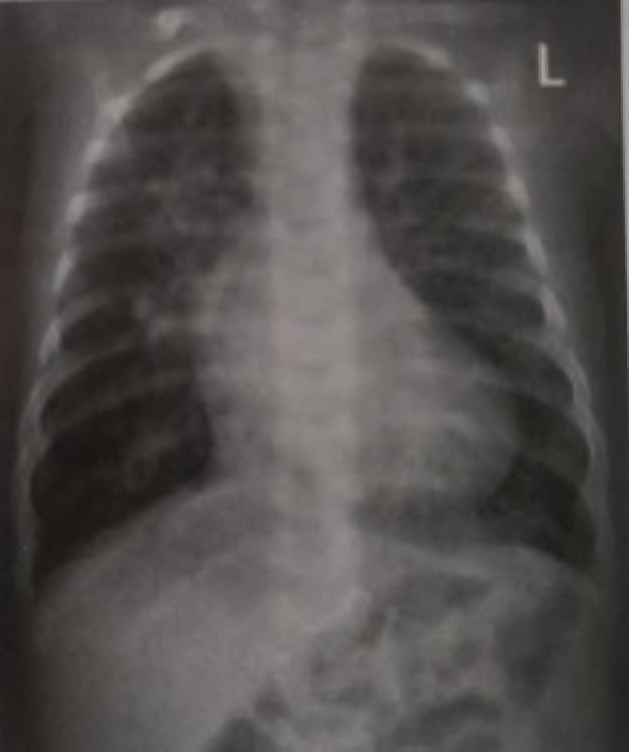

Recém-nascido com idade gestacional de 42 semanas, filho de mãe diabética, parto cesárea por pós-datismo e líquido amniótico meconial (+++/4+). Evolui com cianose central, FC: 120 bpm, FR: 65 ipm. Após ser colocado em halo respiratório com oferta de oxigênio a 100%, manteve cianose central e saturação de 60%. Gasometria arterial mostrou: pH: 7,25, pCO2: 42, pO2: 40, bic: 15, BE: -10 e SatO2: 57%. Realizada radiografia de tórax, conforme abaixo.

A conduta imediata neste momento é: